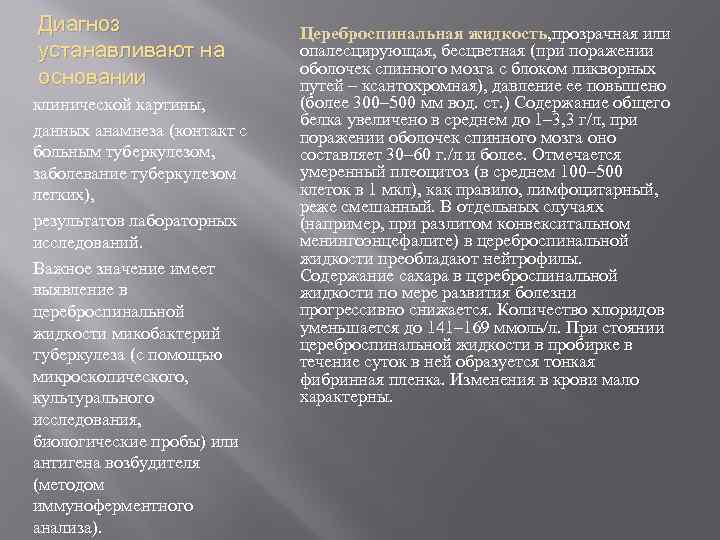

Диагноз устанавливают на основании клинической картины, данных анамнеза (контакт с больным туберкулезом, заболевание туберкулезом легких), результатов лабораторных исследований. Важное значение имеет выявление в цереброспинальной жидкости микобактерий туберкулеза (с помощью микроскопического, культурального исследования, биологические пробы) или антигена возбудителя (методом иммуноферментного анализа). Цереброспинальная жидкость, прозрачная или опалесцирующая, бесцветная (при поражении оболочек спинного мозга с блоком ликворных путей – ксантохромная), давление ее повышено (более 300– 500 мм вод. ст. ) Содержание общего белка увеличено в среднем до 1– 3, 3 г/л, при поражении оболочек спинного мозга оно составляет 30– 60 г. /л и более. Отмечается умеренный плеоцитоз (в среднем 100– 500 клеток в 1 мкл), как правило, лимфоцитарный, реже смешанный. В отдельных случаях (например, при разлитом конвекситальном менингоэнцефалите) в цереброспинальной жидкости преобладают нейтрофилы. Содержание сахара в цереброспинальной жидкости по мере развития болезни прогрессивно снижается. Количество хлоридов уменьшается до 141– 169 ммоль/л. При стоянии цереброспинальной жидкости в пробирке в течение суток в ней образуется тонкая фибринная пленка. Изменения в крови мало характерны.

Диагноз устанавливают на основании клинической картины, данных анамнеза (контакт с больным туберкулезом, заболевание туберкулезом легких), результатов лабораторных исследований. Важное значение имеет выявление в цереброспинальной жидкости микобактерий туберкулеза (с помощью микроскопического, культурального исследования, биологические пробы) или антигена возбудителя (методом иммуноферментного анализа). Цереброспинальная жидкость, прозрачная или опалесцирующая, бесцветная (при поражении оболочек спинного мозга с блоком ликворных путей – ксантохромная), давление ее повышено (более 300– 500 мм вод. ст. ) Содержание общего белка увеличено в среднем до 1– 3, 3 г/л, при поражении оболочек спинного мозга оно составляет 30– 60 г. /л и более. Отмечается умеренный плеоцитоз (в среднем 100– 500 клеток в 1 мкл), как правило, лимфоцитарный, реже смешанный. В отдельных случаях (например, при разлитом конвекситальном менингоэнцефалите) в цереброспинальной жидкости преобладают нейтрофилы. Содержание сахара в цереброспинальной жидкости по мере развития болезни прогрессивно снижается. Количество хлоридов уменьшается до 141– 169 ммоль/л. При стоянии цереброспинальной жидкости в пробирке в течение суток в ней образуется тонкая фибринная пленка. Изменения в крови мало характерны.